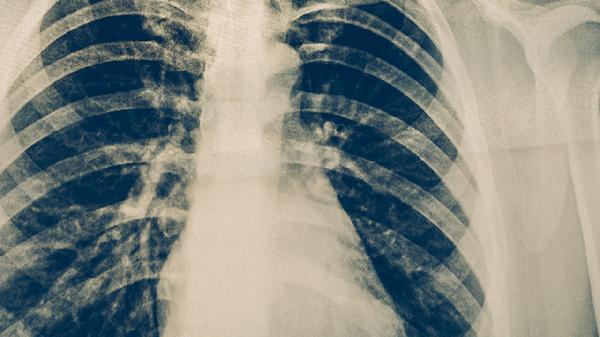

肺結(jié)核的常見(jiàn)病因主要有結(jié)核分枝桿菌感染、免疫功能低下、密切接觸傳染源、營(yíng)養(yǎng)不良以及合并慢性疾病等。肺結(jié)核是由結(jié)核分枝桿菌引起的慢性傳染病,主要通過(guò)呼吸道傳播,當(dāng)人體免疫力下降時(shí)容易發(fā)病。

結(jié)核分枝桿菌是肺結(jié)核的主要致病菌,可通過(guò)飛沫傳播進(jìn)入人體肺部。感染后細(xì)菌在肺泡內(nèi)繁殖,導(dǎo)致肺部出現(xiàn)炎癥反應(yīng)和壞死。結(jié)核分枝桿菌具有抗酸性,可在體內(nèi)長(zhǎng)期存活,當(dāng)機(jī)體免疫力下降時(shí)容易發(fā)病。治療需使用異煙肼片、利福平膠囊、吡嗪酰胺片等抗結(jié)核藥物聯(lián)合用藥。

慢性阻塞性肺疾病、塵肺、矽肺等肺部疾病患者易合并肺結(jié)核。這些疾病導(dǎo)致肺部防御功能受損,為結(jié)核菌生長(zhǎng)繁殖創(chuàng)造條件。糖尿病患者血糖控制不佳時(shí)也容易并發(fā)肺結(jié)核。治療時(shí)需要同時(shí)控制基礎(chǔ)疾病和抗結(jié)核治療。